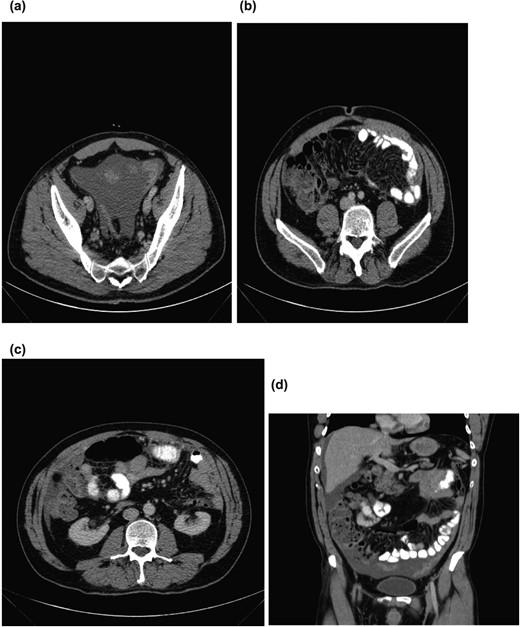

On initial examination, he was pale looking, afebrile and vitally stable; the abdomen was soft but distended. His initial blood investigations revealed microcytic hypochromic anaemia with haemoglobin of 9.2 mg/dl, low serum iron, transferrin, and ferritin, and high CRP (187 mg/l). Further workup was started with gastroscopy and colonoscopy, which were normal, followed by CT-TAP that showed multiple mesenteric implants with omental caking and gross ascites. No primary tumour localization was identified (Fig. 1a–d).

(a) Pelvic ascites. (b) Axial section showing omental caking. (c) Axial section showing omental caking. (d) Sagittal section showing peritoneal nodularity and ascites.